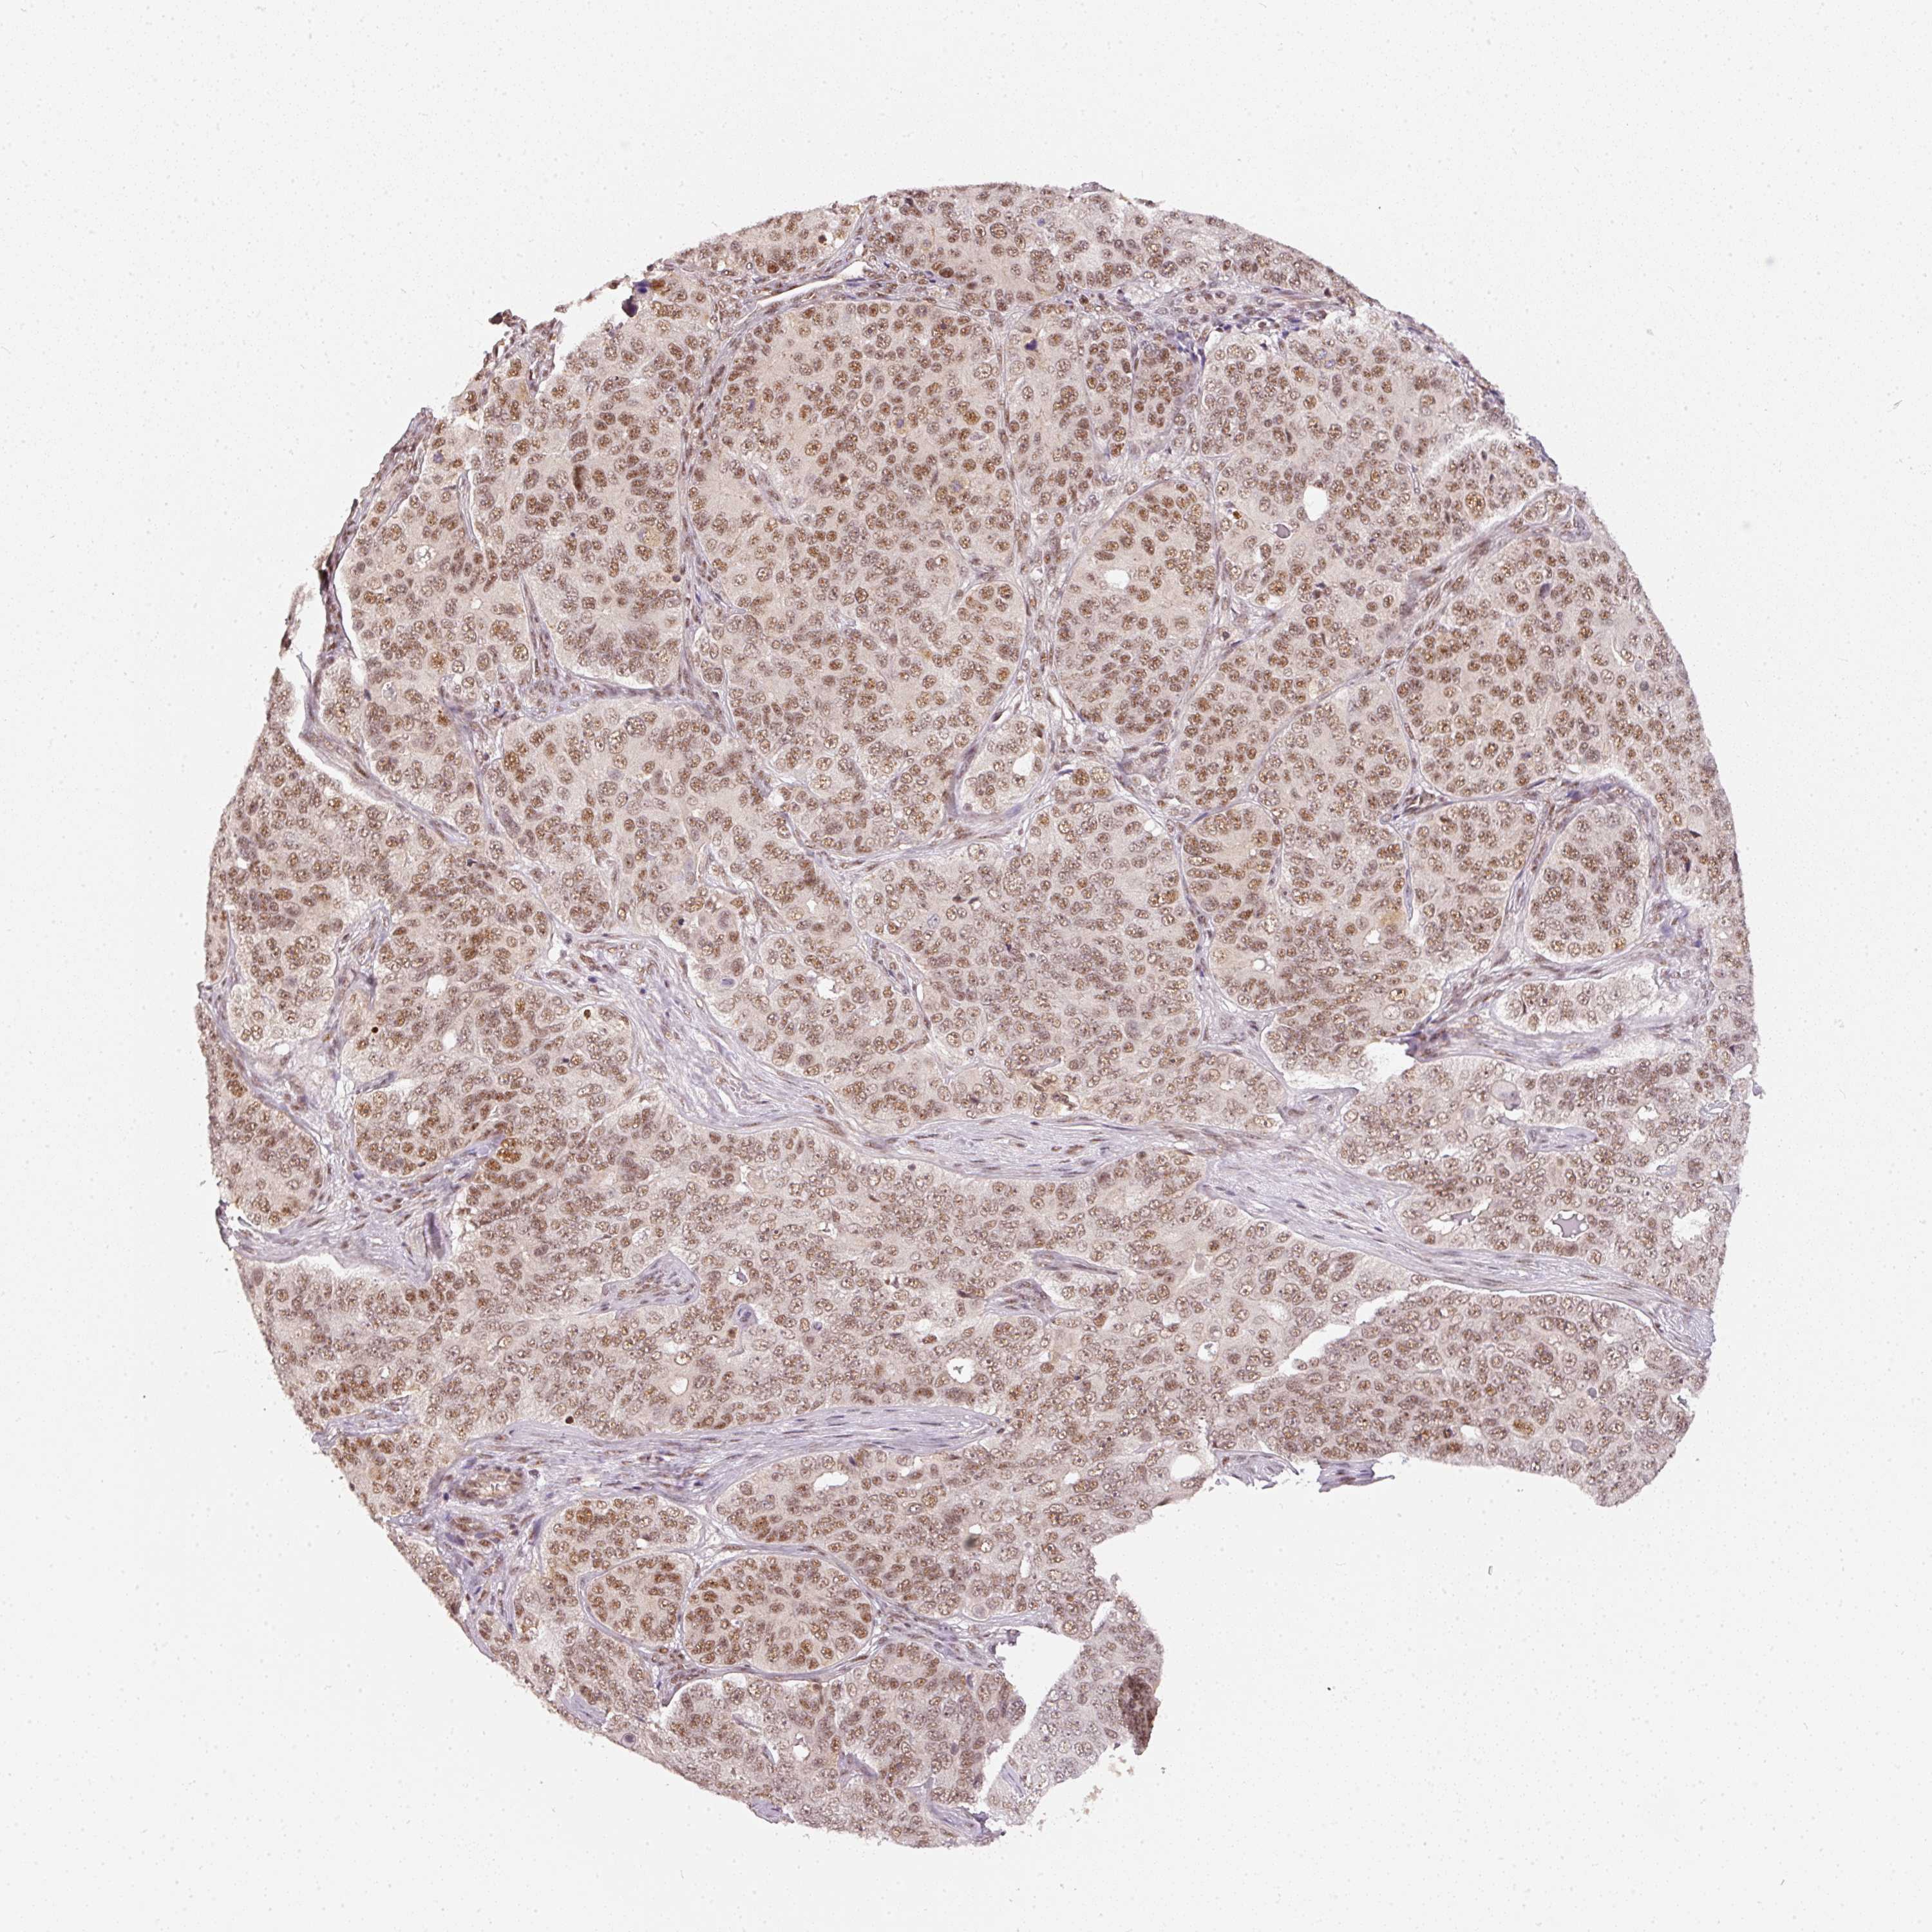

OVARIAN CANCER - Protein expressioni

A mouse-over function shows sample information and annotation data. Click on an image to view it in a full screen mode. Samples can be filtered based on level of antibody staining by selecting one or several of the following categories: high, medium, low and not detected. The assay and annotation is described here.

Note that samples used for immunohistochemistry by the Human Protein Atlas do not correspond to samples in the TCGA dataset.

Antibody stainingi

Antibody staining in the annotated cell types in the current human tissue is reported as not detected, low, medium, or high, based on conventional immunohistochemistry profiling in selected tissues. This score is based on the combination of the staining intensity and fraction of stained cells.

Each image is clickable and will lead to virtual microscopy that enables deeper exploration of all samples and also displays staining intensity scores, fraction scores and subcellular localization as well as patient and tissue information for each sample.

Antibody HPA052953

Staining

High

Medium

Low

Not detected

Intensity

Strong

Moderate

Weak

Negative

Quantity

>75%

75%-25%

<25%

None

Location

Nuclear

Cytoplasmic/membranous

Cytoplasmic/membranous,nuclear

Cystadenocarcinoma, serous, NOS

Carcinoma, endometroid

Cystadenocarcinoma, mucinous, NOS

Carcinoma, NOS